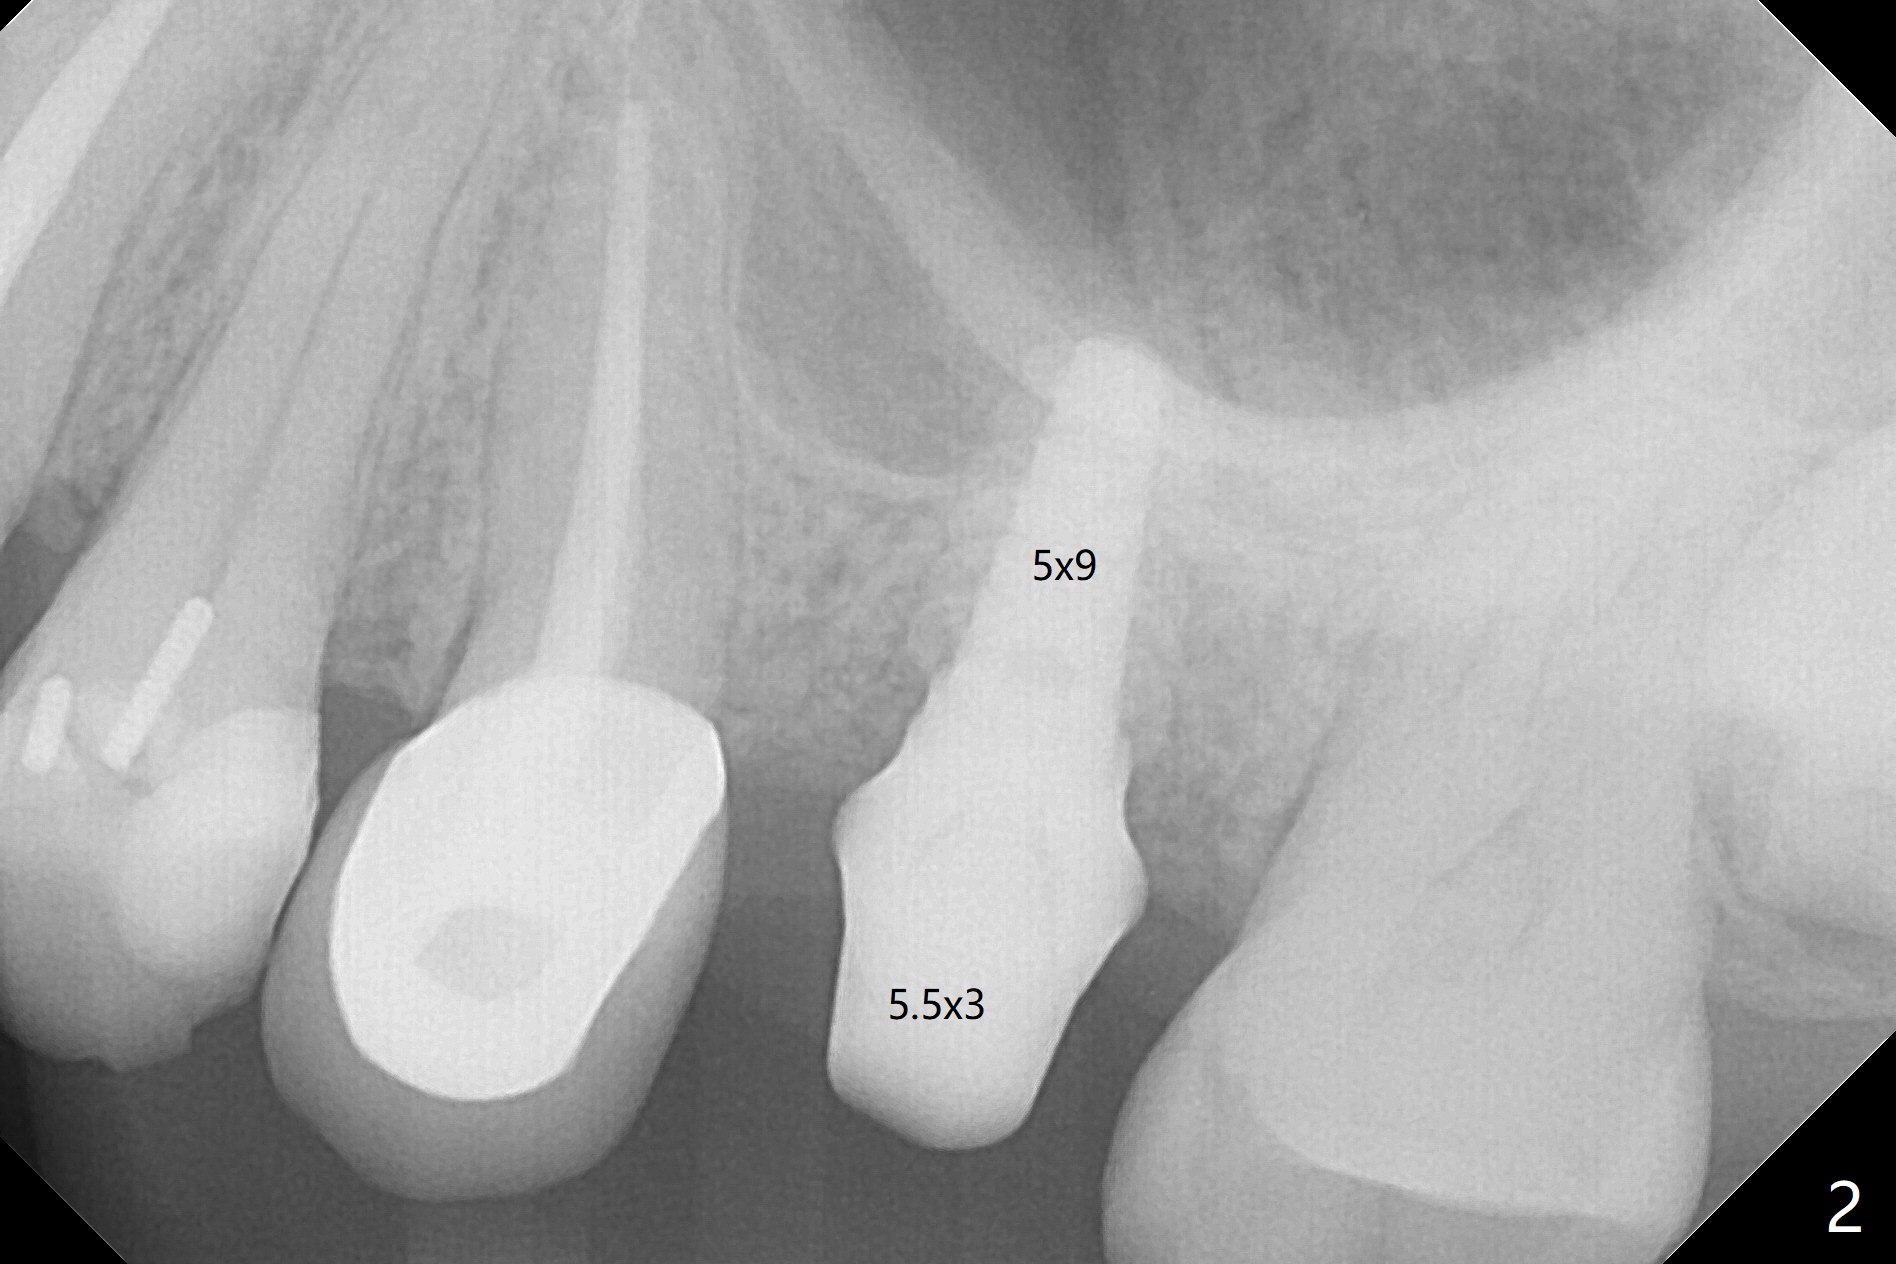

The ridge is wide at #14 11 months post socket preservation. Access and bone expansion (BEB) starts with Magic Split, followed by Magic Expanders 3.0, 3.8 and 4.3 mm from 8 to 9 mm for sinus lift. No bone is removed for osteotomy. Instead bone condensation occurs. After placement of a 4.5x11 mm dummy FC implant (Fig.1 with sinus lift (without bone graft)), a 5x9(2) mm Magicore (2 mm cuff) is placed with >55 Ncm with cuff margin at the gingival margin (Fig.2); a 5.5x3 mm solid abutment tries in. There is no occlusal clearance; trimming of the solid abutment will be needed. Later a healing screw is placed (Fig.3 *). There is no bone loss 5.5 months postop (Fig.4). A healing cap is placed without much tissue blanching. Instead a 5.5x3 mm solid abutment is placed; after height adjustment, impression is taken. A permanent crown is temporarily cemented 6 months postop (to rule out food impaction) and permanently re-cemented 7 months postop (Fig.5,6). CBCT taken 3-4 months post cementation shows that the implant threads are within the bone (Fig.7) and that the implant barely enters the sinus (Fig.8 *). That is significant since the patient has chronic sinusitis with thickened sinus membrane (Fig.9 *). The tooth #18 seems to have crazing line 10 months post cementation of the crown at #14 (overloading, Fig.10).